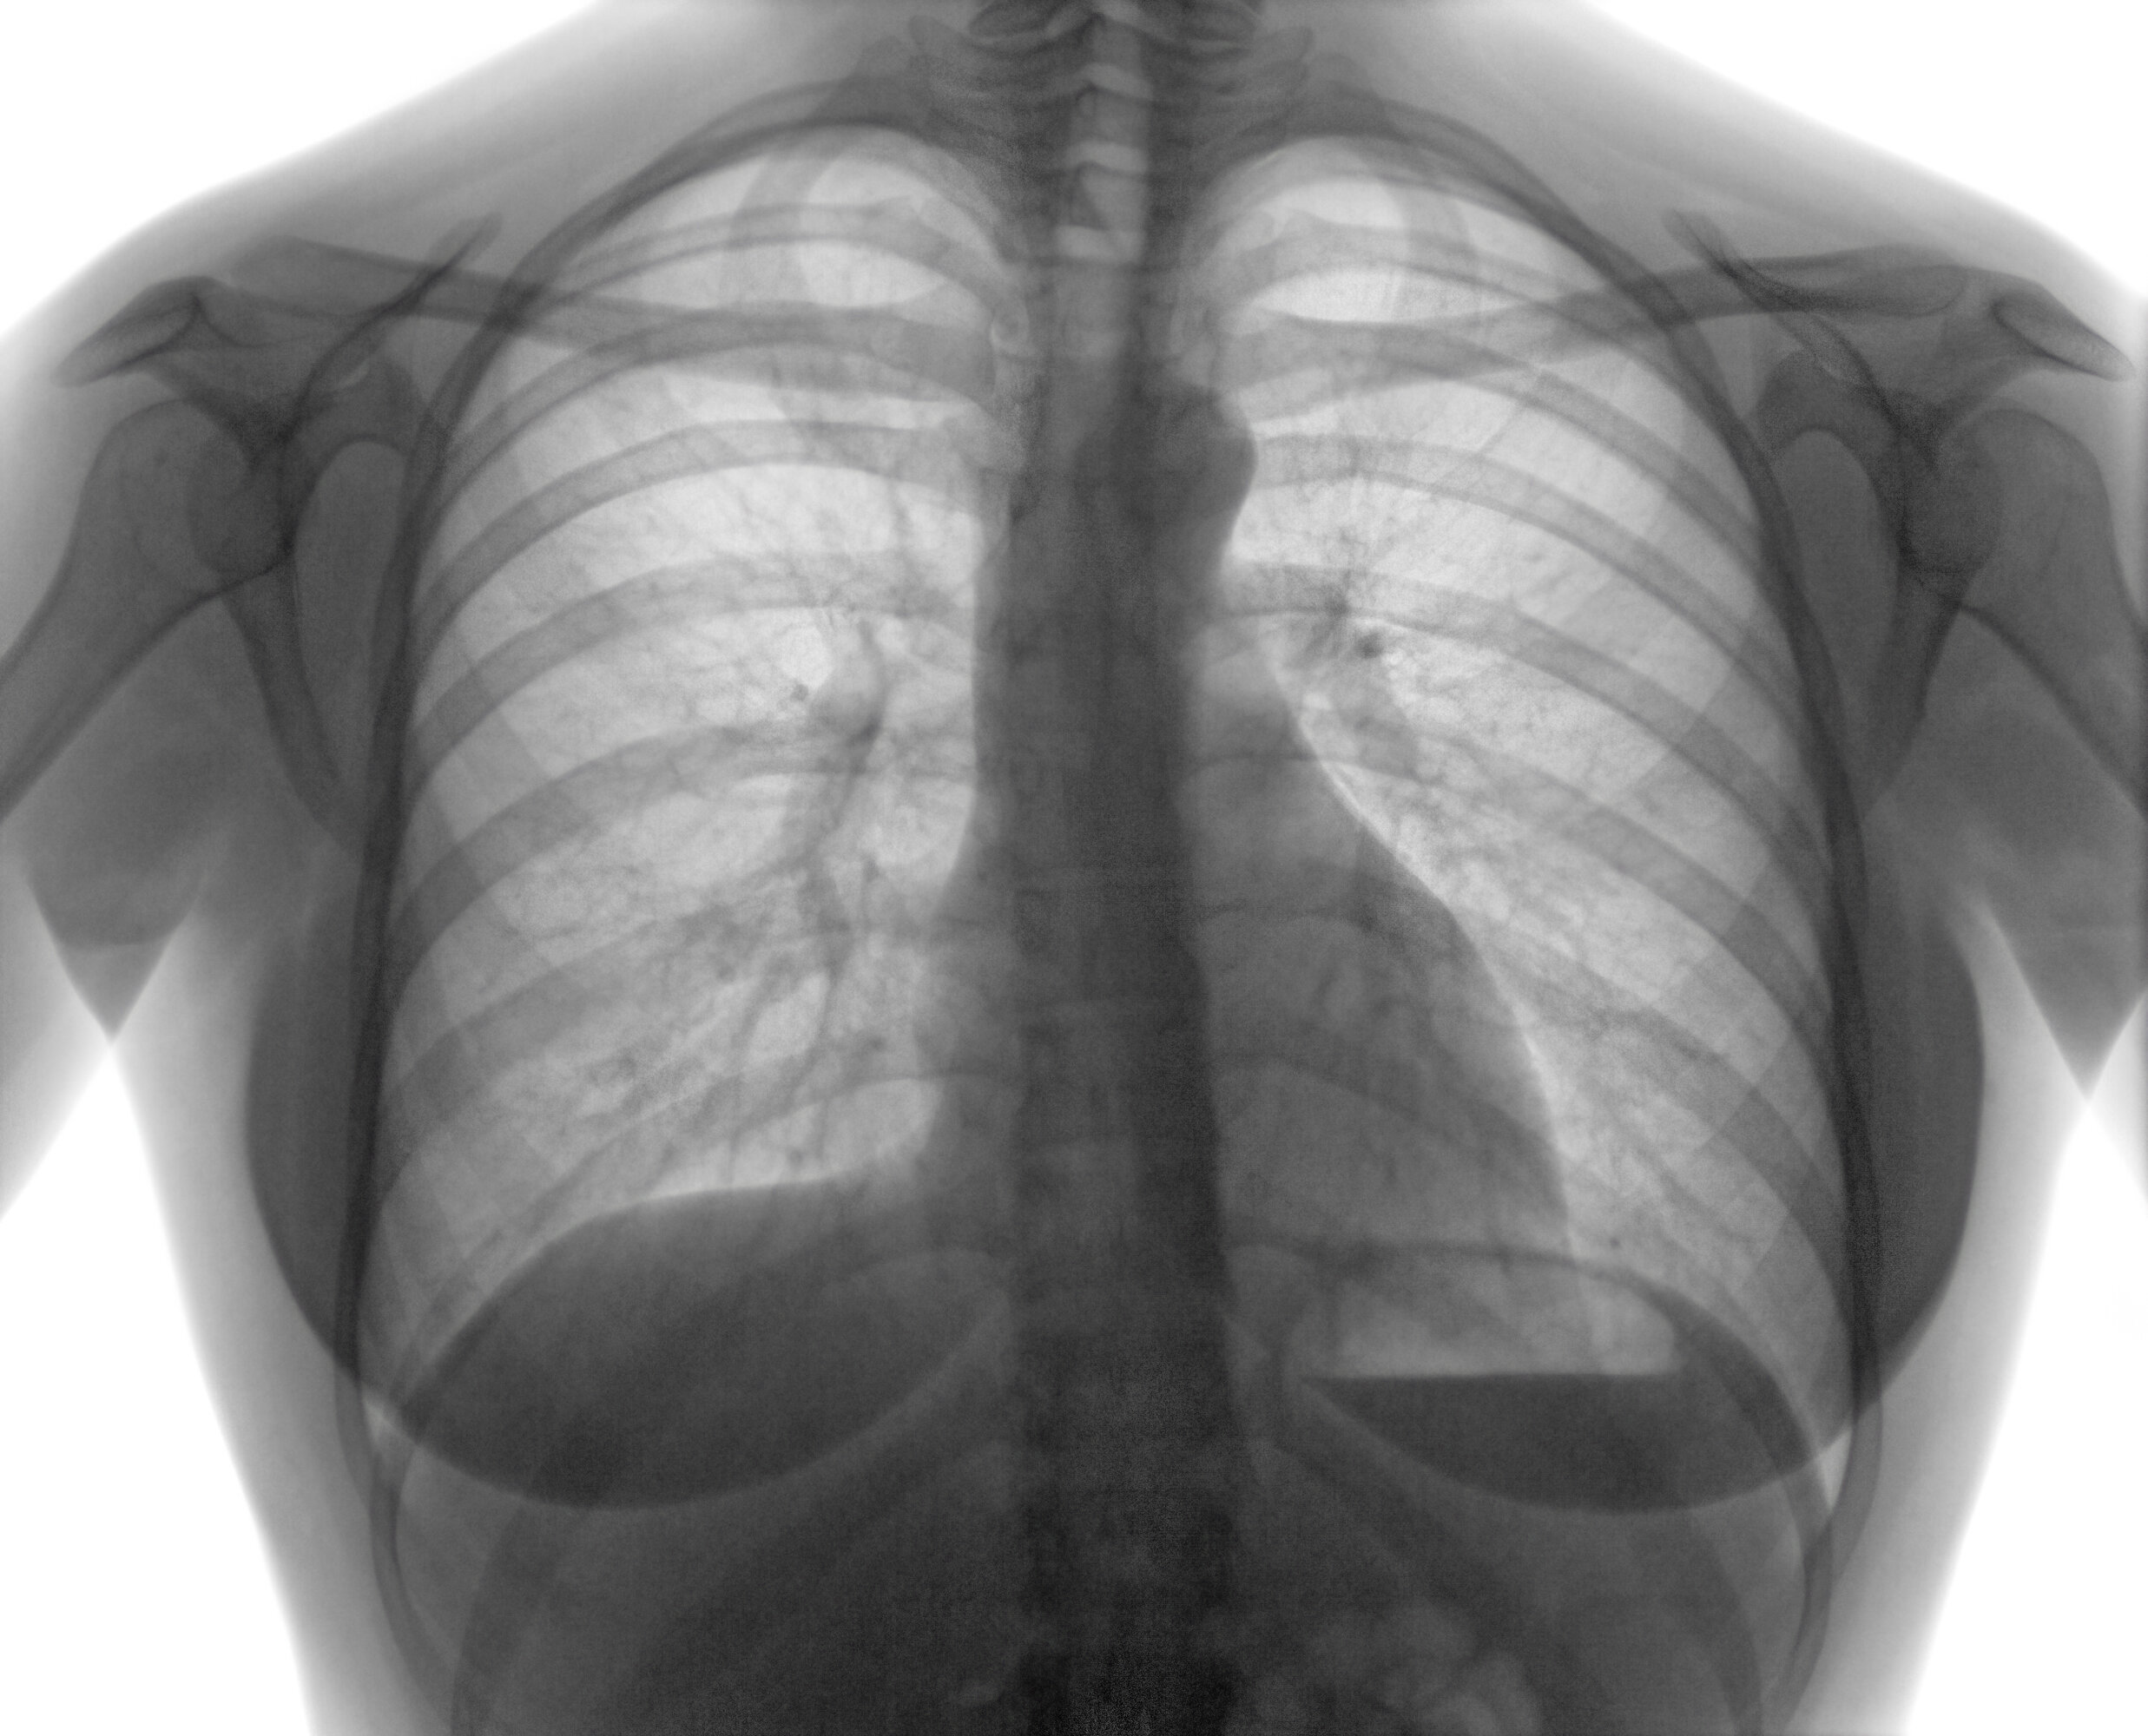

De acordo com a enfermeira coordenadora do Programa Municipal de Tuberculose, Marlene Terezinha Boreck, a Tuberculose é uma doença infecciosa que atinge principalmente os pulmões, mas também pode ocorrer nos gânglios, rins, ossos, meninges e outros locais do organismo. “A nossa intenção enquanto profissionais da saúde é a divulgação e sensibilização sobre os principais sinais e sintomas da doença, para que casos sejam captados precocemente e também desmistificar pré conceitos relacionados a ela”, afirma.

O principal sintoma é a tosse por mais de três semanas. E quanto antes a pessoa com tuberculose for tratada, mais simples a sua cura.